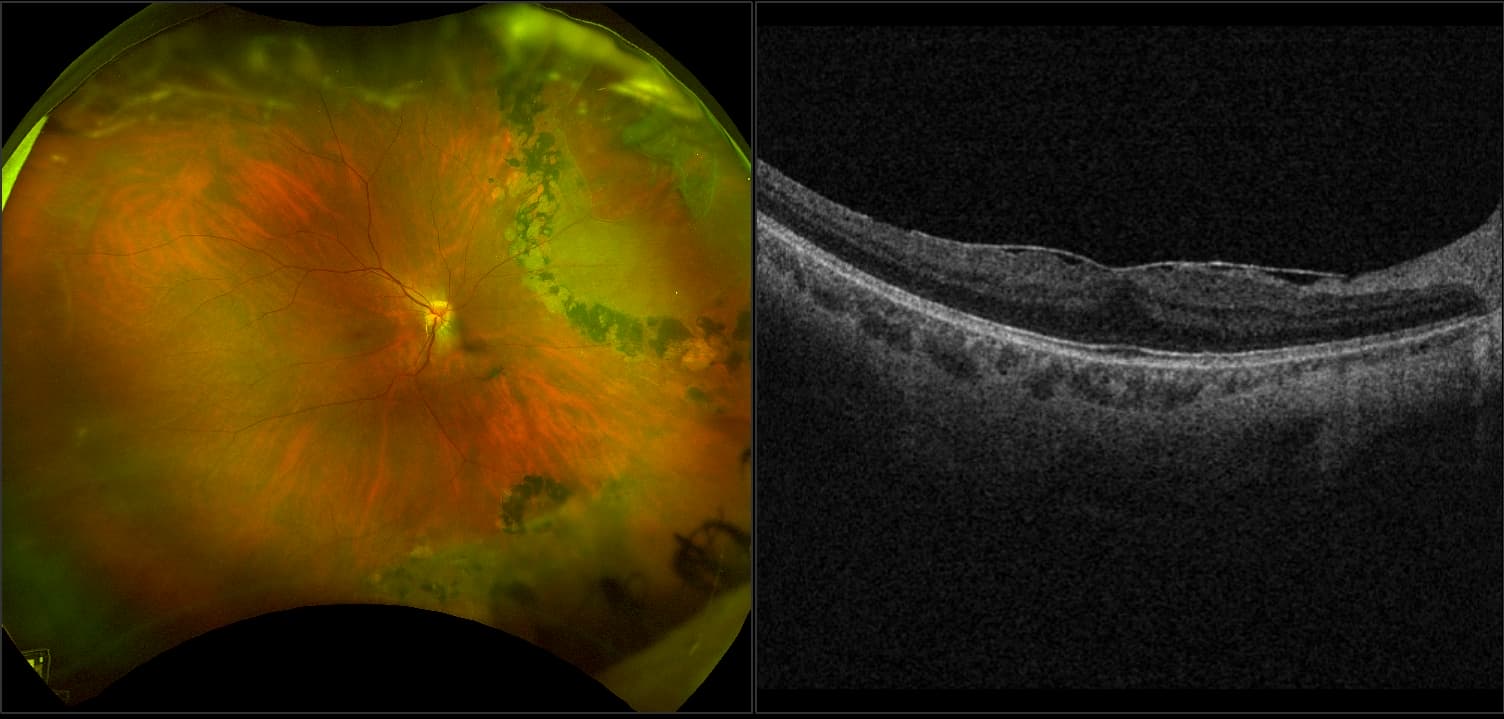

Abbildung 1. Ultra-Weitwinkel-Bildgebung des Augenhintergrundes mit integrierter Swept-Source-Optischer-Kohärenztomografie (Silverstone).

Die Ultra-Weitwinkel-Bildgebung erweist sich als besonders wertvoll im Myopie-Management, da sie periphere Netzhautauffälligkeiten erkennt, die das Risiko für sehbedrohende Komplikationen wie Netzhautablösungen erhöhen. Multimodale UWF-Geräte wie der Optos Silverstone kombinieren die UWF-Bildgebung mit anderen Technologien wie der optischen Kohärenztomografie (OCT), der Fluoreszenzangiografie und der Fundusautofluoreszenz. Diese ermöglichen eine bessere Visualisierung und ein besseres Management von Erkrankungen wie myopischer Makulopathie und Retinoschisis, die mit traditionellen Methoden oft schwer zu erkennen sind.

Die UWF-Bildgebung hat unser Verständnis der Pathophysiologie der Myopie erweitert. Sie hat Zusammenhänge zwischen posterioren Staphylomen und Veränderungen der Choroidea-Dicke aufgezeigt, die als mögliche Prädiktoren für die Krankheitsprogression gelten. Darüber hinaus wurden Bereiche peripherer Avaszularisation sichtbar gemacht. Es ist an der Zeit, dass die UWF-Bildgebung ihren festen Platz im Kampf gegen die Myopie einnimmt.